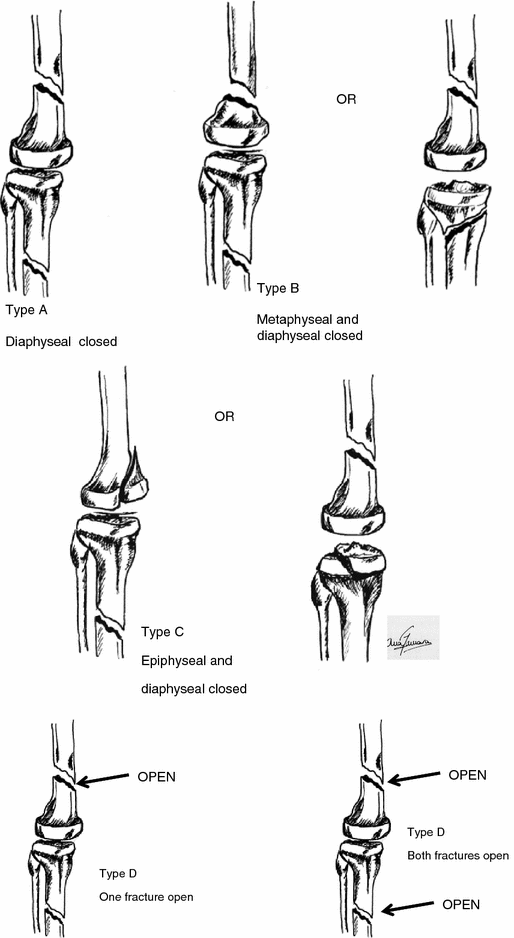

The floating knee epidemiology, prognostic indicators &

The floating knee epidemiology, prognostic indicators & Floating Pieces In Knee If you feel something strange in your knee joint — like something's floating in there — it may be articular cartilage. These fragments can float freely in the joint space and synovial fluid, but they can also become trapped in the knee, causing pain and inflammation. In more severe cases, these symptoms can. Knowing how to identify a loose body. Floating Pieces In Knee.

Floating knee A modified Fraser's classification and the results of a Floating Pieces In Knee Everyone has cartilage in their knees, but there could be an injury that requires. A loose body is essentially a fragment of cartilage or bone that has broken away from the surface of the knee joint. If you feel something strange in your knee joint — like something's floating in there — it may be articular cartilage. These fragments can. Floating Pieces In Knee.

Floating knee A modified Fraser's classification and the results of a Floating Pieces In Knee Loose bodies are another name for free floating pieces of debris in the joint. They are tissues that have torn away from their original location and. Knowing how to identify a loose body in your knee can help you seek out the right support when you’re struggling with a persistent pain. They can be the result of an injury or. Floating Pieces In Knee.